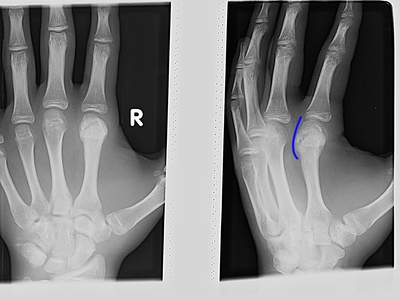

P.S. Снимки прилагаю. Разница во времени между первым и вторым - 25 дней. Был еще снимок в чисто боковой проекции, но его как-то коряво сохранили и я не отыскал его в базе.

Вот здесь

Иллюстрация к комментарию